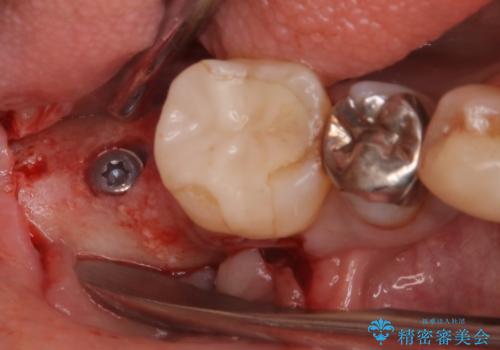

重度の歯周病により保存困難と診断し、抜歯後にインプラント治療を行いました。

抜歯後十分な骨の回復が認められず、単独の骨増生を行った後にインプラントを埋入しました。

インプラント埋入時に骨が足りない場合にはインプラント埋入前に骨増生を行います。また、インプラント周囲の角化歯肉が不足した場合は角化歯肉の移植も行うことがあります。